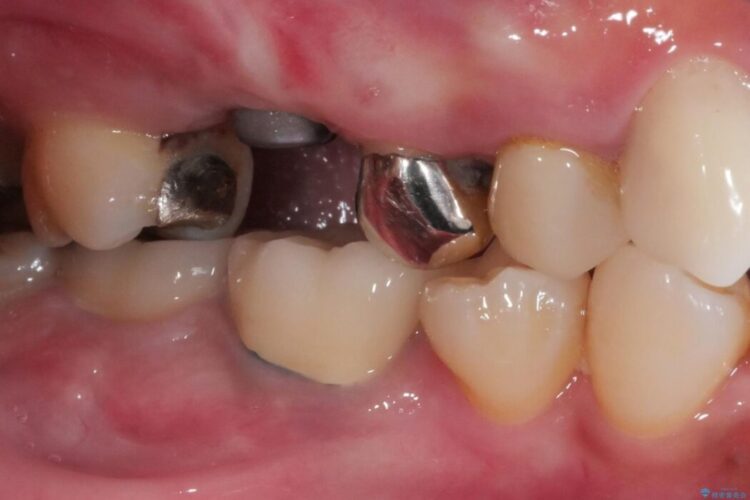

奥歯で噛んだときに違和感があるとご来院された患者様です。

歯根の先端の病変が大きく割れてしまっていた為、残念ながら抜歯の必要がありました。

精密検査の結果、骨の厚みは問題なかったのですが高さは少し低かったので、幅が太い短いインプラントを使って治療を行うこととしました。